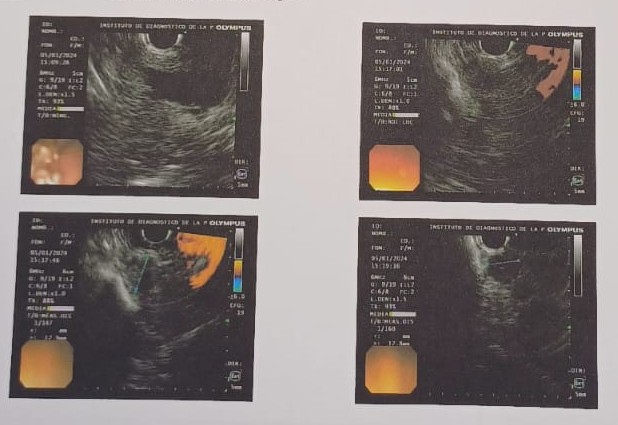

Figure 2: Endoscopic ultrasound-guided fine-needle aspiration (EUS-FNA) cytology of pancreatic insulinoma.

(A–D) Cytological specimens reveal cohesive clusters of monotonous, small-to-medium-sized cells with round nuclei, finely granular chromatin (“salt-and-pepper” pattern), and scant cytoplasm, consistent with a neuroendocrine neoplasm. Immunocytochemical staining shows diffuse positivity for CD56, supporting neuroendocrine differentiation. These findings are compatible with a well-differentiated pancreatic neuroendocrine tumor (insulinoma).

Tumor markers, including carcinoembryonic antigen (CEA), carbohydrate antigen 19-9 (CA 19-9), and chromogranin A, were within normal ranges. In the appropriate clinical context, these findings supported the diagnosis of insulinoma.

For tumor localization, computed tomography (CT), CT angiography, abdominal magnetic resonance imaging, and positron emission tomography (PET) with somatostatin analogs were performed, all of which were inconclusive. Subsequently, ^18F-DOPA PET revealed a focal area of increased uptake in the pancreatic head region. Endoscopic ultrasound (EUS) provided precise anatomical characterization, demonstrating a hypoechoic, round, well-defined lesion located in the pancreatic neck, measuring 13 × 12 mm (Fig. 1). EUS-guided fine-needle aspiration was performed, and cytological analysis revealed features consistent with a well-differentiated neuroendocrine tumor. Immunohistochemical evaluation showed a low proliferative index (Ki-67 <3%), consistent with a grade 1 tumor (Fig. 2).